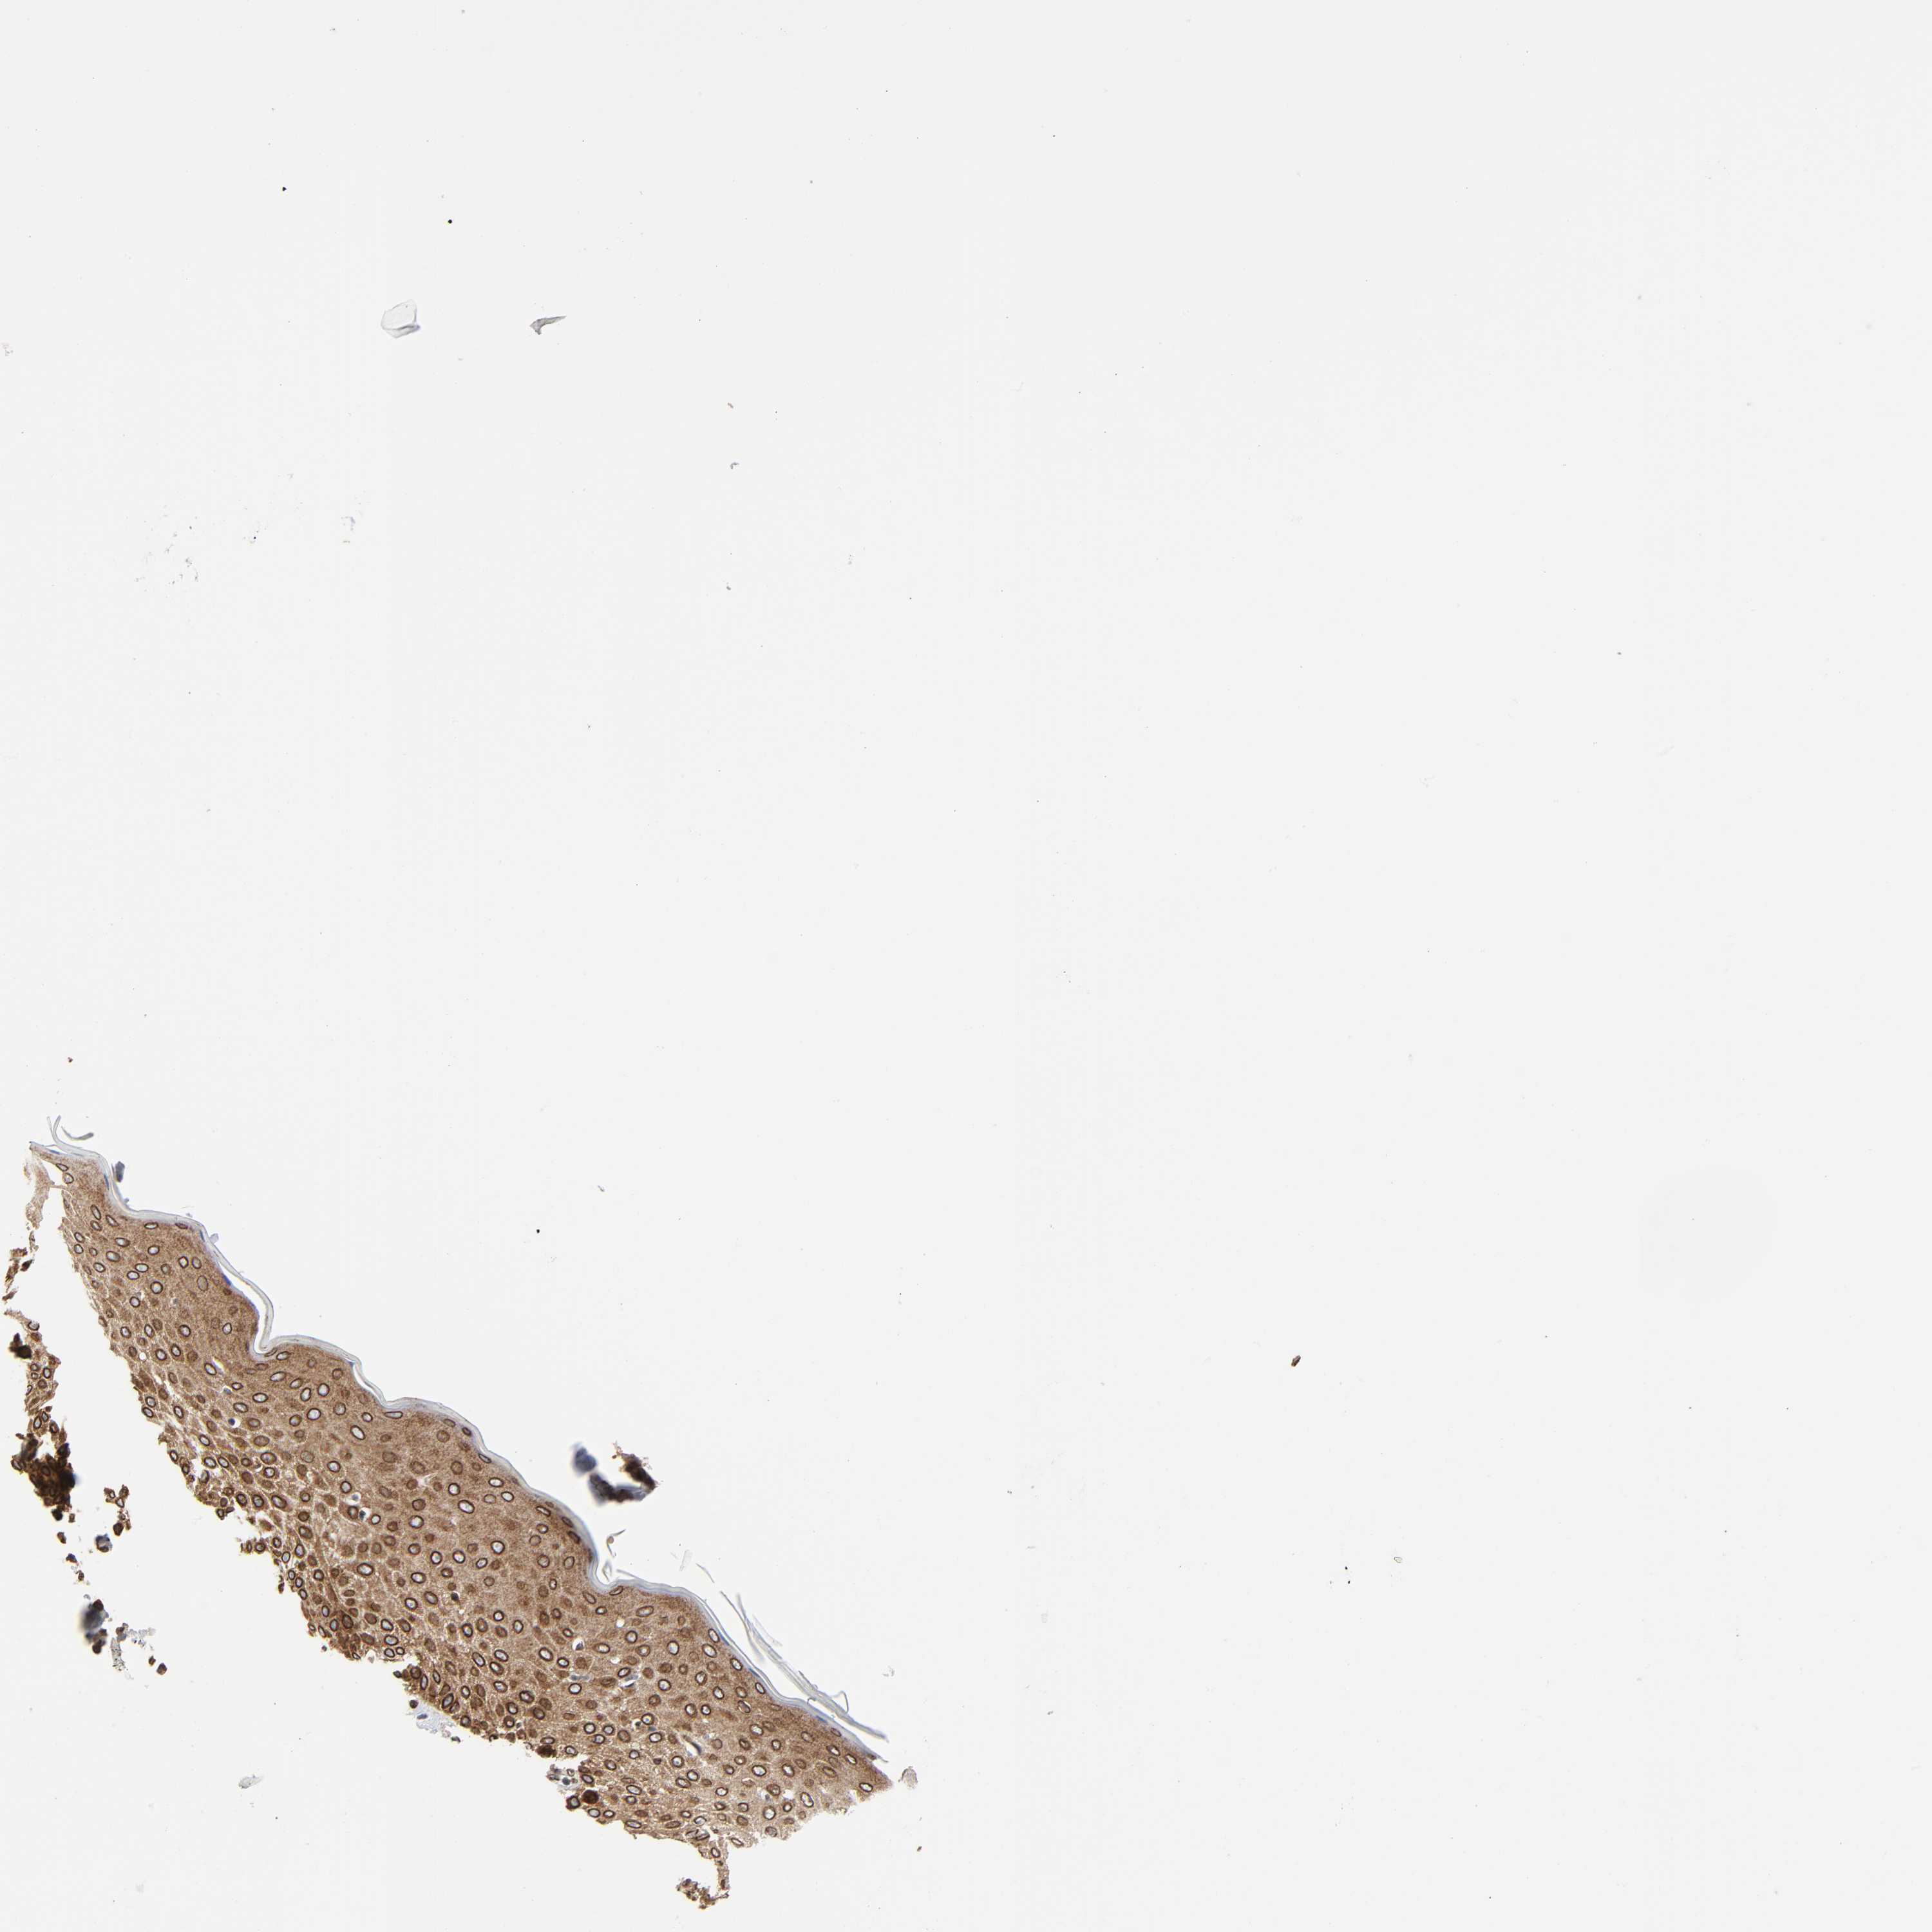

Basal cell and squamous cell cancer

SKIN CANCER - Protein expressioni

A mouse-over function shows sample information and annotation data. Click on an image to view it in a full screen mode. Samples can be filtered based on level of antibody staining by selecting one or several of the following categories: high, medium, low and not detected. The assay and annotation is described here.

Antibody stainingi

Antibody staining in the annotated cell types in the current human tissue is reported as not detected, low, medium, or high, based on conventional immunohistochemistry profiling in selected tissues. This score is based on the combination of the staining intensity and fraction of stained cells.

Each image is clickable and will lead to virtual microscopy that enables deeper exploration of all samples and also displays staining intensity scores, fraction scores and subcellular localization as well as patient and tissue information for each sample.

Antibody HPA050110

Antibody CAB004293

Basal cell carcinoma